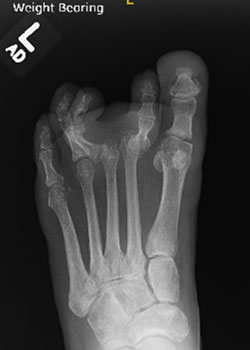

Lapiplasty Bunion Surgery with Dr. Teichman - BeforeBefore

Lapiplasty Bunion Surgery with Dr. Teichman - AfterAfter